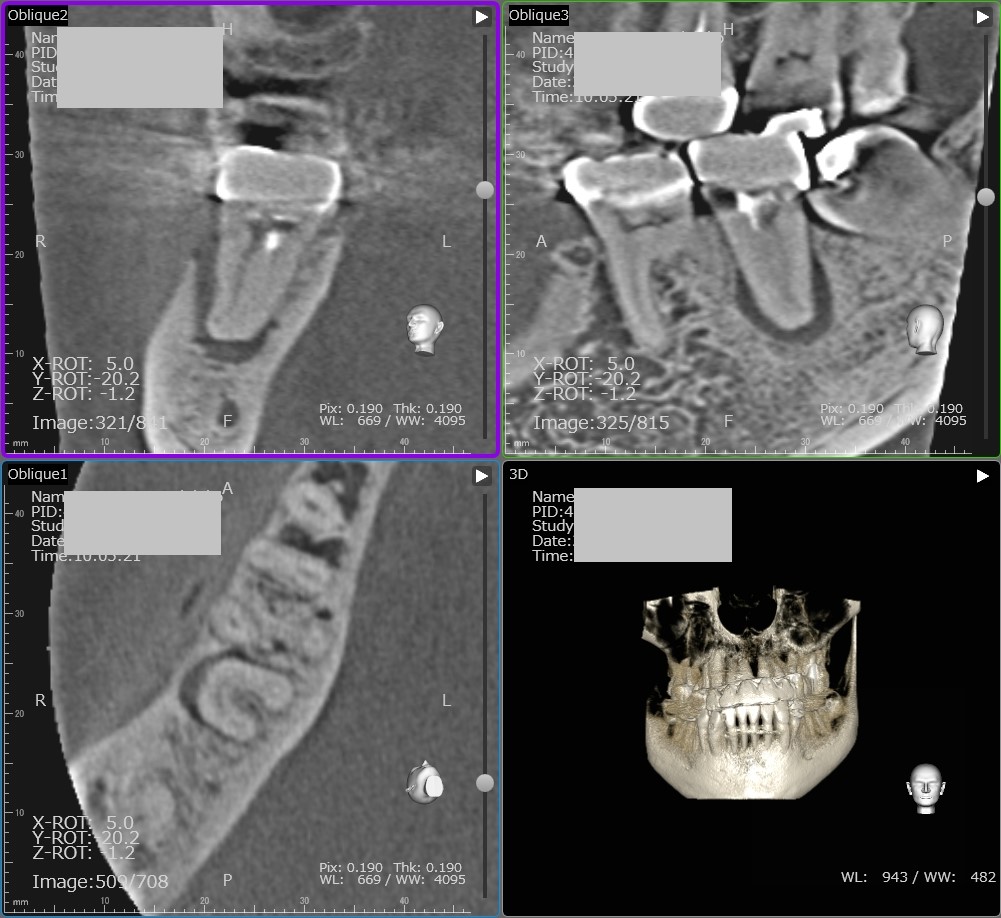

上顎奥歯の根管治療 ファイル破折除去

さて 今回は奥歯の根管治療の症例を紹介します。